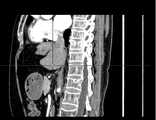

Figure 8b is a schematic representation of a sequence of CT images viewed from the sagittal plane.

fig. 8a-8c are raw three-dimensional data of sequential CT images viewed from three directions, the transverse, sagittal and coronal planes, respectively. Fig. 9a to 9c are the second binarized images obtained after the method removes the bed plate area, respectively, and it can be seen from fig. 9a to 9c that none of the skin surface contours of the human body area is damaged. Fig. 10a to 10c are respectively third binarized images obtained after filling the cavity by the method, and it can be seen from fig. 10a to 10c that the third binarized images are completely overlapped with the original three-dimensional data of the sequence CT image, and the lung region with a low threshold value is effectively filled. As can be seen from FIGS. 11a-11d, after another serial CT image is reconstructed by the method, the three-dimensional model of the skin can be fused with the third binary image and the serial CT image. And finally mapping the obtained three-dimensional model of the skin back to a 2D mode, and comparing the coincidence degree of the skin boundary in the three-dimensional model of the skin and the binary image to obtain figures 12a-12 c. In addition, the three-dimensional models of the skin of other parts of the human body obtained by the method are shown in figures 13a-13 c.